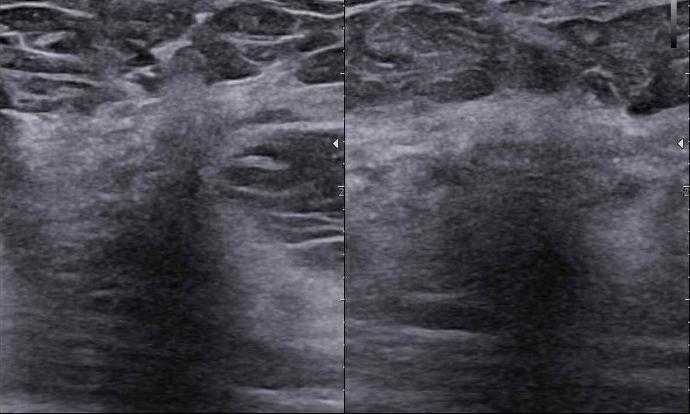

Czy podział BIRADS 4 ma sens?

Jak radzić sobie z BIRADS 4a, b, c? – morfologiczne wskazówki

Ultrasonografia jest jedną z czterech głównych metod w diagnostyce chorób piersi. Współczesna sytuacja epidemiologiczna, czyli ciągły wzrost zachorowań na raka piersi u kobiet, wymaga od nas dyskusji na ten temat.